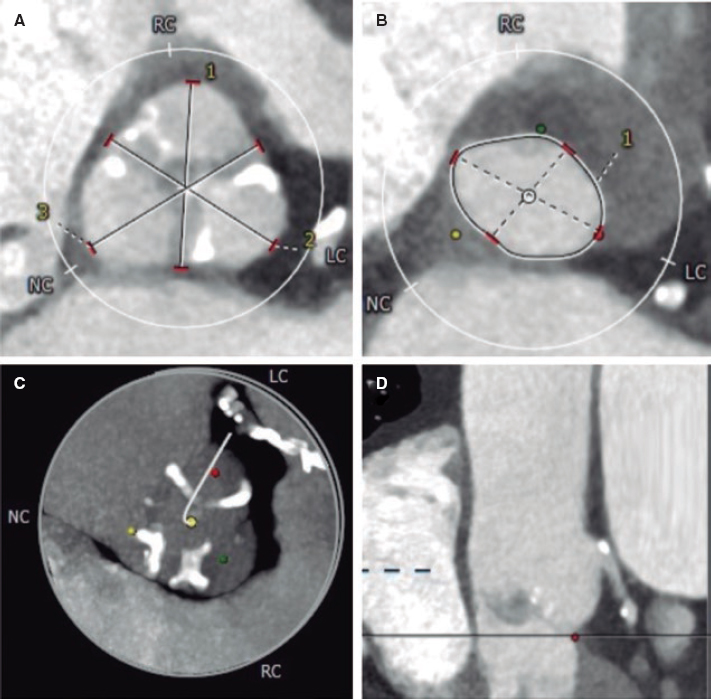

Predilatation occurred in 32 lesions (51.6%) and postdilatation in 37 (59.7%). The criterion used for postdilatation was angiography guided visual underexpansion. Intravascular ultrasound was performed in 15 patients (30%) before the implant. It was also used in 2 patients to optimize the percutaneous coronary intervention given the persistent stent underexpansion seen on the angiography. In both cases the minimum lumen area was > 5.5 mm2 with stent expansion > 80% and lack of incomplete apposition (defined as a strut separation of > 0.4 mm axial and 1 mm longitudinal) (figure 2). The optical coherence tomography was performed in a patient with ST-segment elevation acute coronary syndrome before and after the implant. It revealed a high thrombotic load with lack of immediate stent malapposition.